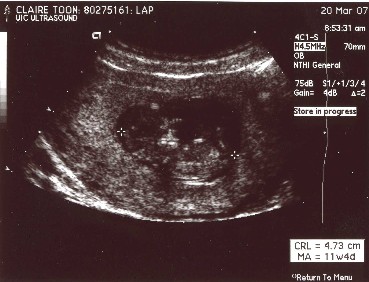

Here are the first pictures of Baby Zen. These ultrasound pictures were taken a few weeks ago at 12 weeks. I don't know about you, but sometimes the ultrasound pictures don't look like much of anything. I've included a guide picture to help you see Baby Zen. Just click on the pictures to make them larger.